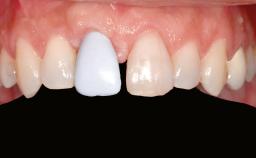

Ridge Preservation and Implant Placement for a Fixed Dental Prosthesis After a Car Accident